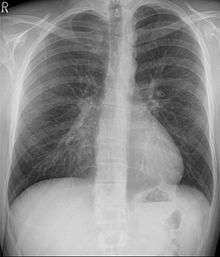

Pectus excavatum is initially suspected from visual examination of the anterior chest. Auscultation of the chest can reveal displaced heart beat and valve prolapse. There can be a heart murmur occurring during systole caused by proximity between the sternum and the pulmonary artery.[17] Lung sounds are usually clear yet diminished due to decreased base lung capacity.[18]

Chest x-rays are also useful in the diagnosis. The chest x-ray in pectus excavatum can show an opacity in the right lung area that can be mistaken for an infiltrate (such as that seen with pneumonia).[22] Some studies also suggest that the Haller index can be calculated based on chest x-ray as opposed to CT scanning in individuals who have no limitation in their function.[23]